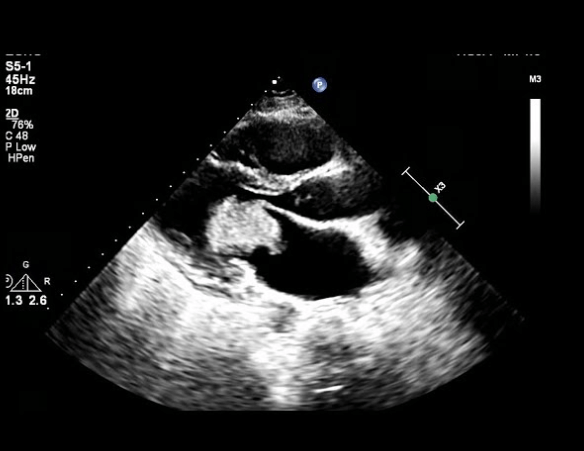

Name of this ultrasound finding of the heart.

What is a cardiac myxoma?